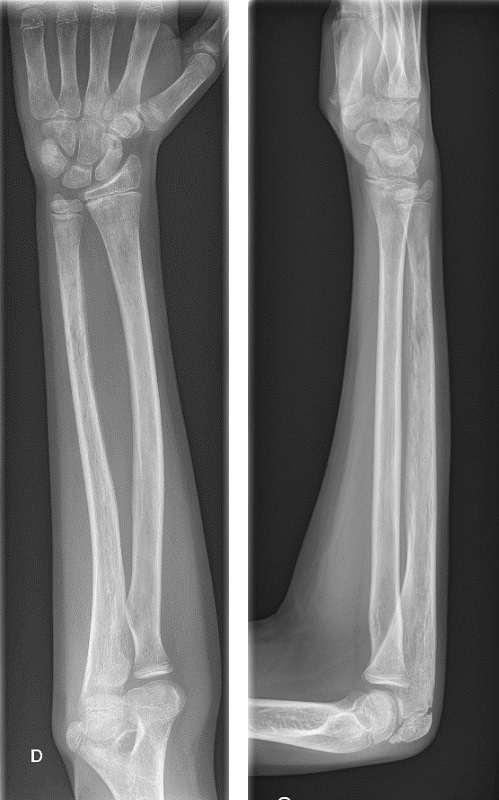

Durante su ingreso en planta, se realiza gammagrafía ósea (Fig. 2) en la que se aprecia inflamación de 2.ª articulación metacarpofalángica, junto con aumento del remodelado óseo de cúbito distal derecho, por lo que se realiza radiografía de antebrazo Fig. 3), en la que presenta un patrón óseo permeativo y apolillado con reacción perióstica en cúbito, que impresiona de posible infiltración medular.

| Figura 3. Radiografía de muñeca y antebrazo derechos al ingreso. Cúbito con patrón óseo permeativo y apolillado con reacción perióstica |

Las lesiones óseas en la leucemia son más frecuentes en niños que en adultos. Pueden deberse tanto a la propia infiltración tumoral como al tratamiento con quimioterapia y corticoides. La gammagrafía es más sensible en estadios iniciales, pudiendo demostrar alteración en la captación hasta en un 75% de las leucemias agudas al diagnóstico. Sin embargo, estos hallazgos no son específicos, y no siempre se correlacionan con alteraciones en la radiografía ni con la localización del dolor4,12. En el caso de nuestro paciente, las pruebas de imagen tuvieron un papel fundamental, ya que, ante el hallazgo de captación en la gammagrafía a nivel del antebrazo, se realizó una radiografía, en la que presentaba patrón permeativo y apolillado en cúbito, con reacción perióstica, que dio la pista definitiva para el diagnóstico.